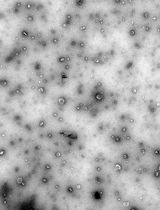

EVs play important roles in health and disease, but their small size, heterogeneity, and variable autofluorescence make analysis challenging [2]. Several techniques have been developed for EV analysis, including electron microscopy, nanoparticle tracking analysis, tunable resistive pulse sensing, western blotting, and ELISA-based assays, each with advantages and limitations [1]. Existing EV isolation protocols, including ultracentrifugation, precipitation, and size-exclusion chromatography, often face challenges such as incomplete removal of contaminating platelets, co-isolation of protein aggregates, variable EV recovery, and loss of vesicles during multiple washing steps [3]. Moreover, differences in centrifugation speeds, buffer preparation, and gating strategies limit reproducibility across laboratories [4]. Flow cytometry–based detection adds further complexity due to EV heterogeneity, variable autofluorescence, and the difficulty of distinguishing true EVs from debris [5].